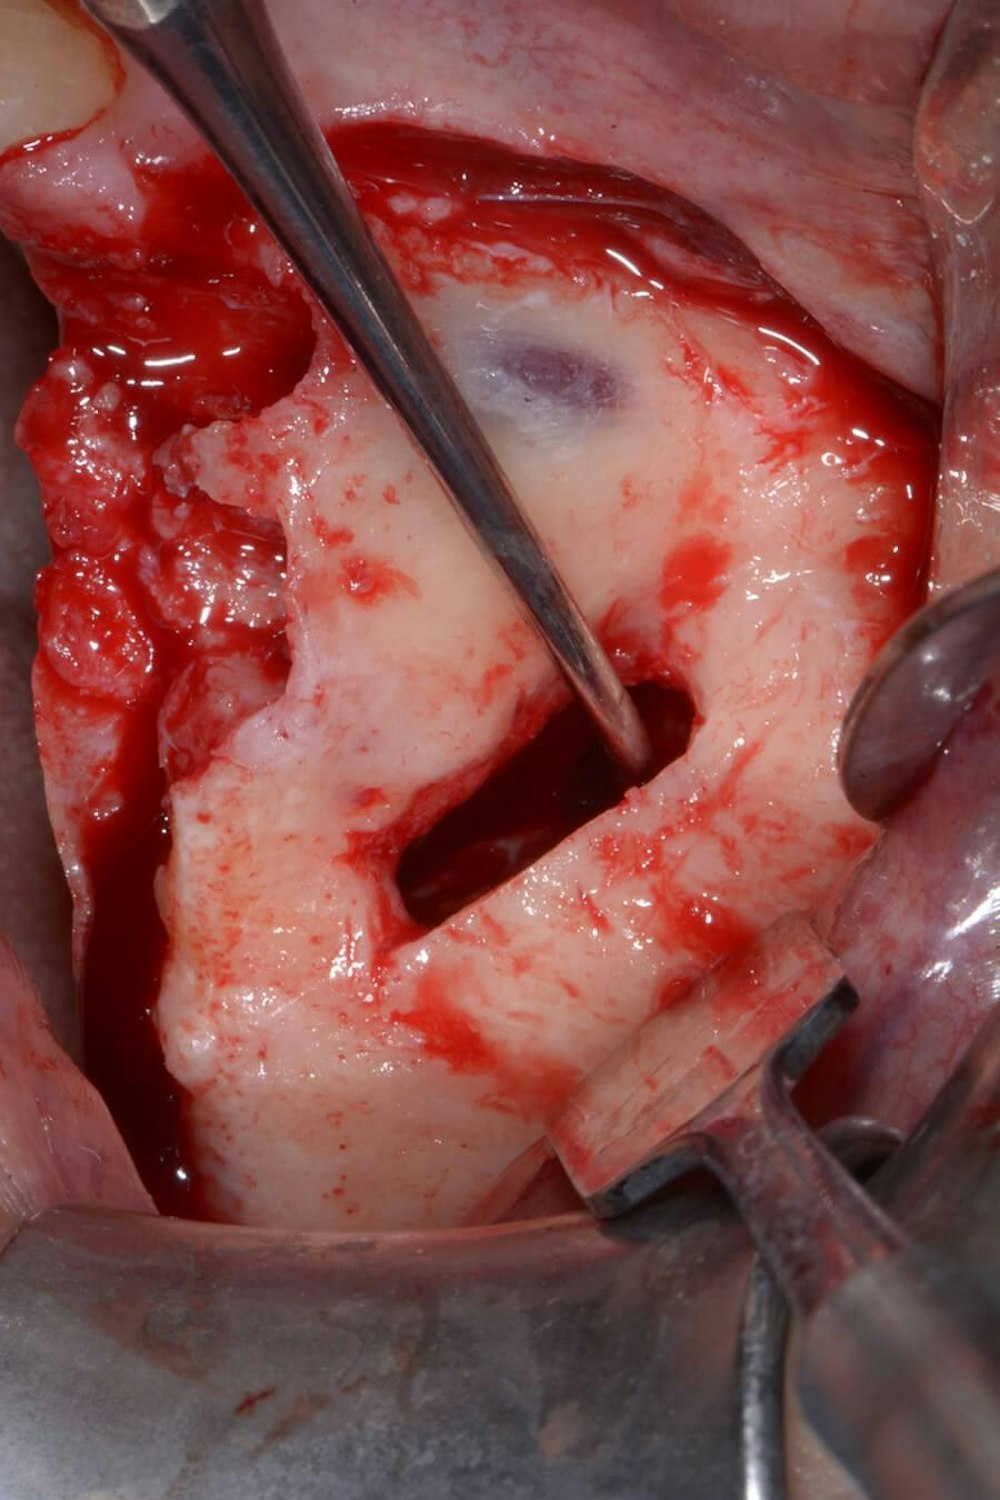

An incision is made along the crest with vertical releasing incisions to obtain access to the lateral and anterior walls of the sinus. The extension of the flap is smaller than a traditional sinus elevation. Once a full-thickness flap is elevated, a small antrostomy is made parallel to the anterior sinus wall starting 3 mm distal to it and then extending anteriorly to reach the anterior sinus wall. The antrostomy is usually 4 to 6 mm mesiodistally and 7 to 8 mm apicocoronally. This simplified antrostomy design is preferred because extension of the antrostomy to the anterior wall renders the membrane elevation procedure simpler and safer by providing direct visual access to the narrow anterior portion of the sinus. This results in a reduced membrane perforation rate (Fig 2a-b).

The antrostomy is parallel to the anterior sinus wall. The membrane has been distally displaced and the nasal mucosa is gently elevated to allow implant site preparation.

Distal displacement of the sinus membrane allows for the placement of an implant with a distal tilt of 30 degrees (Fig. 3). The direction of the first implant drill can be observed through the antrostomy. The preparation of the implant site extends apically through the anterior sinus wall into the cortical layer of the often adjoining lateral nasal wall. After verification of the implant axis using direction indicators, the drilling sequence is finalized and a bone substitute is inserted (on average, 1 mL of graft material is needed). The implant is then inserted through the residual crestal bone into the grafted sinus where the membrane has been previously displaced distally. It engages apically at the M point, the confluence of three cortical walls. In some cases, it may be possible to obtain satisfactory implant stability without engaging the lateral nasal wall cortex. This approach further simplifies the surgical procedure.

The implant drill is used at a 30 degree angle.